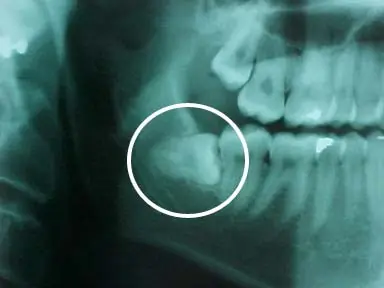

Informe: Muela de juicio

Existen cuatro muelas cordales, una por cada cuadrante bucal, y se sitúan en la última posición de la línea de la dentadura, al fondo de la boca. Las muelas del juicio suelen afectar a otros dientes al desarrollarse, empujándolos o saliendo "torcidas".

· El desarrollo de quistes y tumores se menciona a menudo, pero esto es muy raro que se de. Los quistes a menudo se confunden con otras características normales en las radiografías. Los tumores se encuentran en menos de un por ciento de las muelas de juicio.